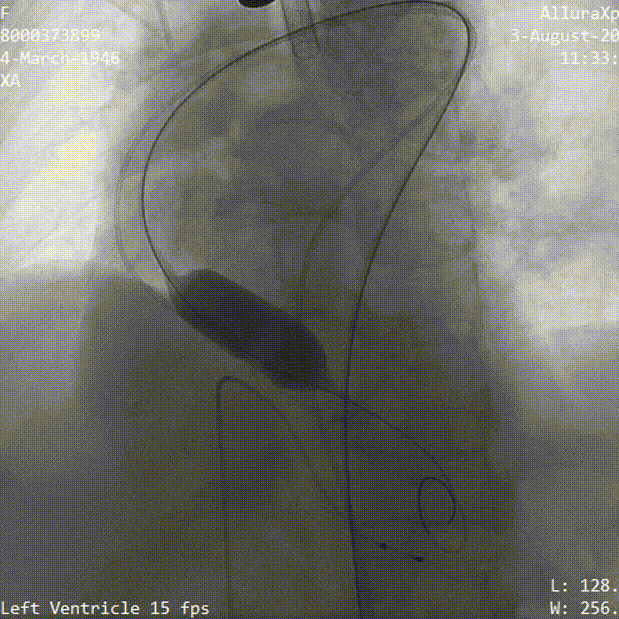

冠脉灌注良好

瓣膜稳定脱钩过程

最终位造影 形态良好 位置理想

无瓣周漏 即刻跨瓣压差为3mmHg